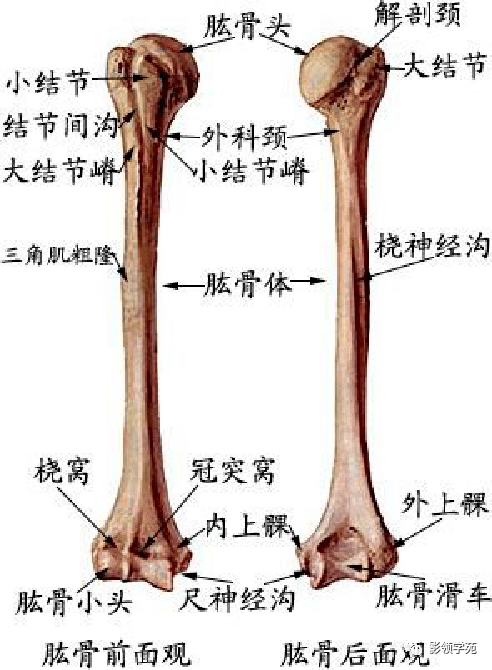

骨骼系统

骨骼系统